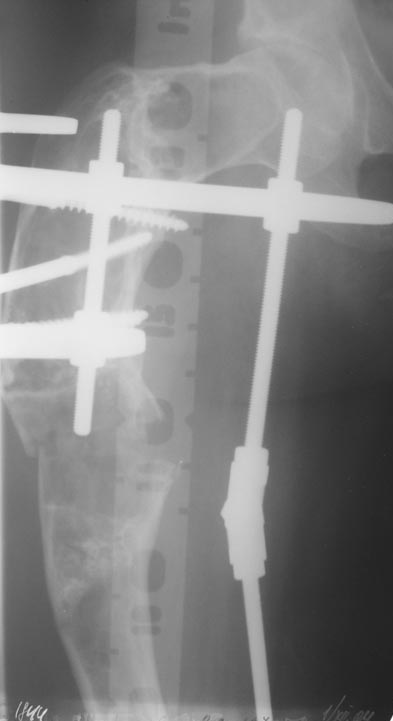

В ноябре этого года я обращался с просьбой о помощи в выборе тактики лечения больной с деформацией бедра на почве фиброзной дисплазии. Были получены интересные и очень полезные советы по операции.

Операция выполнялась с помощью А.Н.Челнокова. Очень понравилась технология выполнения блокируемого остеосинтеза с использованием спицевого дистрактора, модифицированный гвоздь с латерализованным проксимальным отделом и возможностью многовинтовой фиксации проксимального и дистального участков бедра.